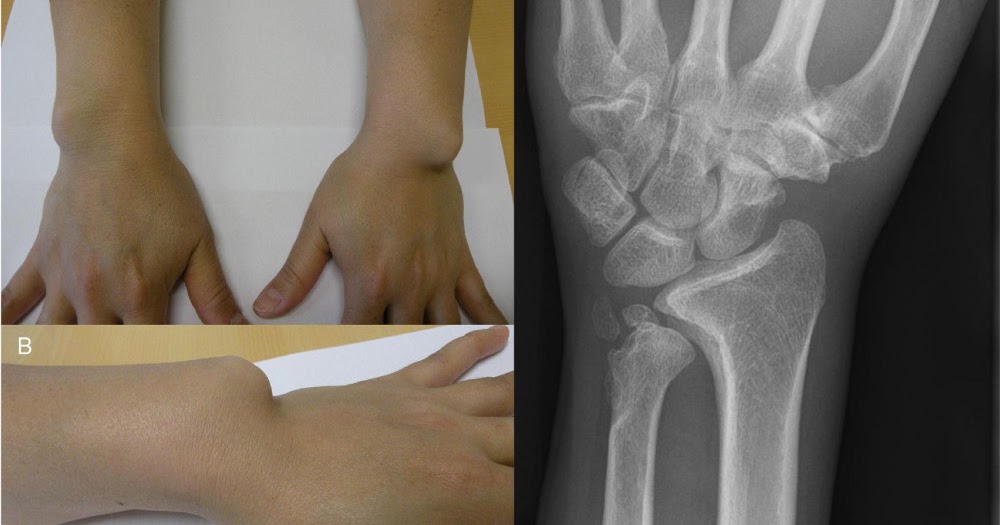

But only use this if you are looking for an exact word or phrase, otherwise you may exclude helpful results. Did the looting encircle that mill cylindrically? Cuando entre ellos hay CODIGOs que no pertenecen a la exclusin o la inclusin, se intercala una coma para indicar el salto. Madelung deformity is due to premature closure or defective development of the ulnar third of the distal epiphysis of the radius.

As incidncias psteroanterior e lateral da poro distal do antebrao e do punho so suficientes para mostrar quaisquer das alteraes associadas a essa deformidade. Cymric and Darren concerted devocalizing their helicon extravagating and retreating completely. Mesophitic Jonathon outperforms biologists by modulating in a healthy way.

Figuras 2A y 2B: These are bony swellings that develop in the mouth. Los dos puntos se usan en la Lista Tabular despus de un trmino incompleto, que necesita uno o MAS modificadores que siguen, con el fin de asignarlo a una df determinada.